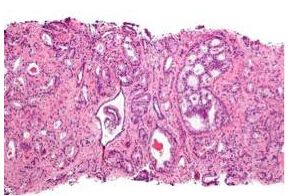

穿刺活检的前列腺肿瘤组织,可经显微成像鉴别出其最常见的癌症类型。而新的液体活检技术的使用,或可以通过非侵入、无创伤的方式诊断和监测癌症。Nephron供图,Wikimedia.